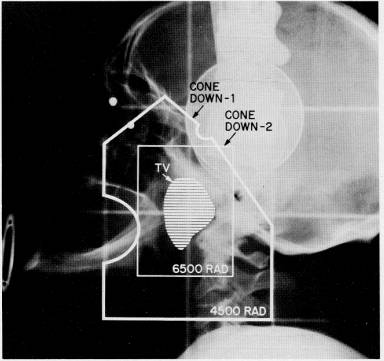

see radiation

port field#1, #2,

#3

radiation isodose #1 , #2, #3, #4, #5 |